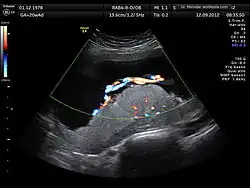

The anomaly scan, also sometimes called the anatomy scan, 20-week ultrasound, or level 2 ultrasound, evaluates anatomic structures of the fetus, placenta, and maternal pelvic organs. This scan is an important and common component of routine prenatal care.[1] The function of the ultrasound is to measure the fetus so that growth abnormalities can be recognized quickly later in pregnancy, to assess for congenital malformations and multiple pregnancies, and to plan method of delivery.[2]

Two-dimensional (2D) is used to evaluate fetal structures, placenta, and amniotic fluid volume. Maternal pelvic organs are also evaluated. Views are obtained using an abdominal ultrasound probe, but a vaginal ultrasound probe may also be used to evaluate for placenta previa and cervical length. Three-dimensional (3D) ultrasound is not recommended for routine use during anomaly scan, but 3D ultrasound may be used to further evaluate suspected abnormalities in specific fetal features.[3]